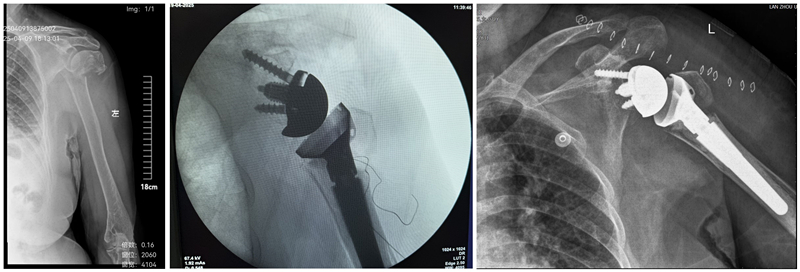

患者为72岁女性,因外伤致左肱骨近端骨折,肩关节严重损伤,导致患者肩关节功能丧失。入院后积极完善相关检查,诊断为肱骨近端骨折、肩袖损伤(岗上岗下肌断裂,小圆肌损伤)、重度骨质疏松症,经过讨论,团队为患者实施了反式肩关节置换手术,通过旋转中心内移和肱骨侧假体下移,利用三角肌替代肩袖功能,使患者具备更好的肩关节功能。术后,患者肩关节疼痛明显减轻,被动屈伸活动良好,现已治愈出院。

术前、术中、术后